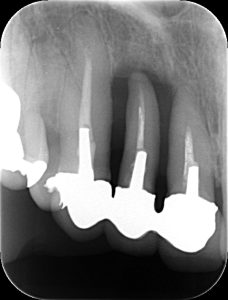

写真の患者さんは、前歯の歯肉がかなり下がっており、クラウンが装着されている3本の歯の中央の歯(側切歯)は、歯槽骨が溶けて全くない状態でした。

レントゲン写真で、歯根の周囲は真っ黒になっています。